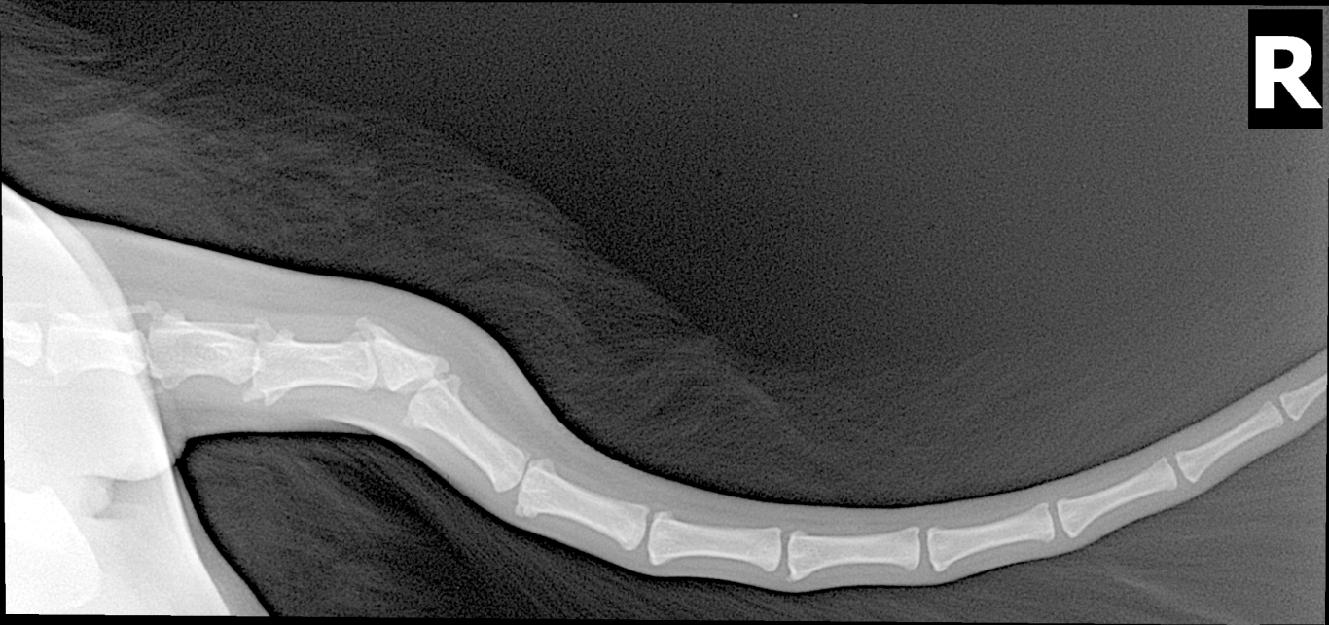

dobrý den,máme 18měs.Howavardku a je hrozně choulostivá na ocas!!!! mává s ním,nic jí nevadí,je veselá při pohybu,hraní nejeví známky,že by něco s ním měla ale nesmíme jí šáhnout na ocas natož učesat,začne se ohánět,točí se kolem jen aby ho schovala,můžeme pouze podrbat na kořeni dál už né!byli jsme na veterině,udělal se rentgén a zjistila se vrozená vada ale údajně to nemá nic společného na to,že si nedá pohladit a učesat,prosím o radu,moc děkuji Smrčková

Dobrý den, určitě to dle mého názoru spojitost má. Doporučila bych zkusit Alavis s látkou MSM (volně dostupný) a znovu navštívit veterinárního lékaře, aby zkusil nasadit léky proti bolesti. Uvidíte jak se to bude vyvíjet dále. Pokud by měla být fenka ale stále bolestivá nejspíš bych zvážila amputaci ocasu. S pozdravem MVDr. Orlovská